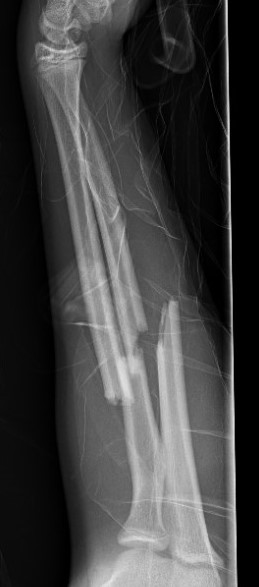

Types

Complete

Greenstick

Buckle / torus

Single or both bone